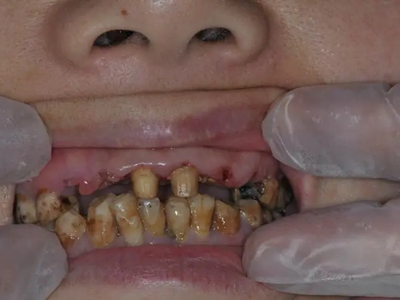

牙齿

牙釉质发育不全牙齿缺损图

牙釉质发育不全磨牙后,牙齿表面的牙冠快磨没了,出现牙齿缺损现象,露出牙髓,缺损面粗糙不平,同时存在牙龈肿胀、牙齿松动或移位等现象,肉眼可见缺损面颜色发黄或发黑。